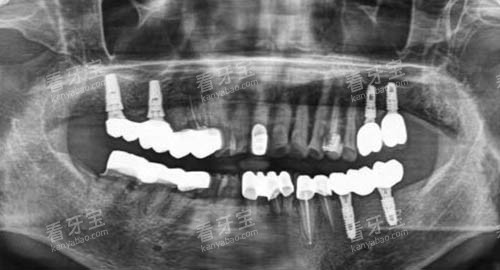

引进了国内外可靠的口腔诊疗设备,如智能化口腔全景机、口腔CT、种植机等。

这些设备能够为医生提供更准的诊断依据,提高治疗的比较准度。

例如,口腔CT可以清晰地显示牙齿的内部结构和周围组织的情况,帮助医生更好地制定种植方案,提高种植成功几率。